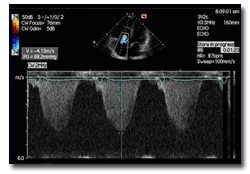

Echokardiografické a Dopplerovské vyšetření jsou nejlepší neinvazivní metody hodnocení plicní hypertenze. Protože většina nemocných má alespoň mírnou trikuspidální regurgitaci, je odhad systolického tlaku v plicnici na základě rychlosti trikuspidální trysky obvykle nejlepší a nejjednoduší metoda ke stanovení diagnózy. V nepřítomnosti trikuspidální regurgitace je měření rychlosti průtoku plicní chlopní spolehlivým prediktorem závažné PH. Doba akcelerace je mírou impedance plicního cévního řečiště a může přinést další informace o funkci pravé komory srdeční. Echokardiografie je velmi dobou metodou pro hodnocení dysfunkce pravé komory srdeční, způsobené plicní hypertenze a její hypertrofie je diagnostikována, přesahuje-li tloušťka její volné stěny 5 mm.

Echokardiografické a Dopplerovské vyšetření